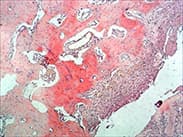

| 高碘酸-Schiff(Periodic acid SchiffPAS法) | 多糖、中性黏液物質(zhì)、酸性黏液物質(zhì) | 肝、腎、心肌、骨骼肌糖原累積癥;骨Ewing氏肉瘤和骨網(wǎng)織肉瘤鑒定 | ![]() |